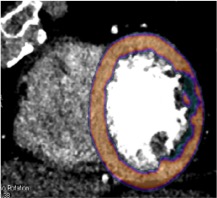

STUDIO DI PERFUSIONE (FASE FUNZIONALE POST-STRESS FARMACOLOGICO)

L’immagine mostra un evidente deficit di perfusione, transmurale, in corrispondenza della parete laterale e postero-laterale del ventricolo sinistro (asse corto ventricolare sinistro, regionale verde scura) nel contesto del miocardio normoperfuso (regioni arancione). Tale deficit è da scriversi alla stenosi identificata sul ramo marginale post-stent in fase anatomica.